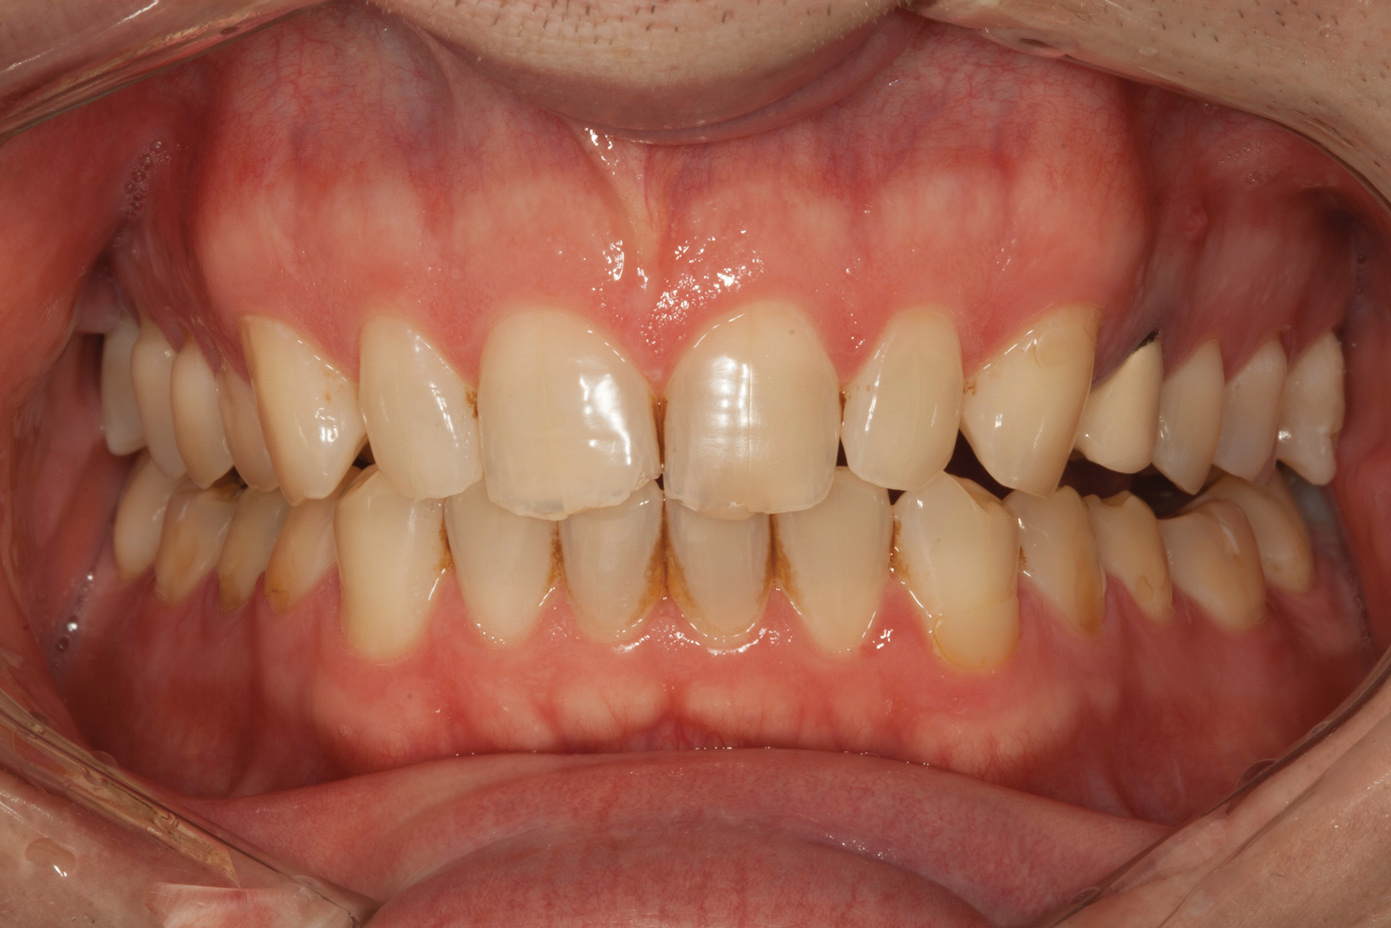

A 34-year-old male patient with no medical issues presented to the office with the chief complaint of a failing crown on tooth No. 12. The patient was also unhappy with his bite and the appearance of his teeth (Figure 1 and Figure 2).

A comprehensive examination was carried out, and preoperative photographs were taken (Figure 1 through Figure 4). The patient presented with fair oral hygiene and slight, generalized tissue inflammation. Caries and defective restorations were detected on teeth Nos. 4, 5, 13, and 14. The crown on tooth No. 12 was showing signs of leakage, and although the endodontic access cavity had been temporarily restored with composite, this endodontic re-treatment was acceptable and the tooth was otherwise symptom-free. Erosion was present on most of the posterior teeth and the cuspids, and abrasion was noted on teeth Nos. 4, 5, 10, 11, 20, 21, 22, 28, and 29. An examination of the patient's muscles, joints, and bite revealed no joint sounds, a normal range of motion, and negative joint load and immobilization tests.

The patient's removable dental orthotic covered the lower bicuspids and first molars. With the orthotic in place, there was shim stock contact on all posterior teeth and on the second molars that were not covered by the appliance. However, there was no incisal overlap and a lack of anterior guidance.9When the orthotic was removed, no more than three teeth touched, and a 2-mm space between the posterior teeth made mastication difficult.

The dentofacial examination revealed a low smile line with no incisor display when the lips were in repose. The anterior teeth were chipped and worn, and their overall color was darkened. The buccal corridors were deficient, and the failing crown on tooth No. 12 was visible in a full smile.

Fig 2. Preoperative retracted view.

Figure 2